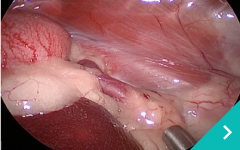

東京どうぶつ低侵襲医療センターでは、大切なご家族である動物たちの体への負担をできる限り軽減するために、 低侵襲(ていしんしゅう)技術を用いた診断・治療を行っています。 内視鏡や腹腔鏡、血管内治療などの先進的な医療機器と専門知識を駆使し、「きずが小さく、痛みが少ない」ことを追求。 術後の回復も早く、入院期間の短縮にもつながります。また、各分野の専門獣医師が連携し、安心・安全なチーム医療を提供しています。

動物たちにやさしく、飼い主さまにも安心していただける医療を目指しています。

腹腔鏡胸腔鏡

診療科目:腹腔鏡・胸腔鏡

『傷』が小さく、『痛み』が少ない手術・検査ができます!!

内視鏡外科(低侵襲)を希望のかたは東京どうぶつ低侵襲医療センター・王子ペットクリニックに相談ください。